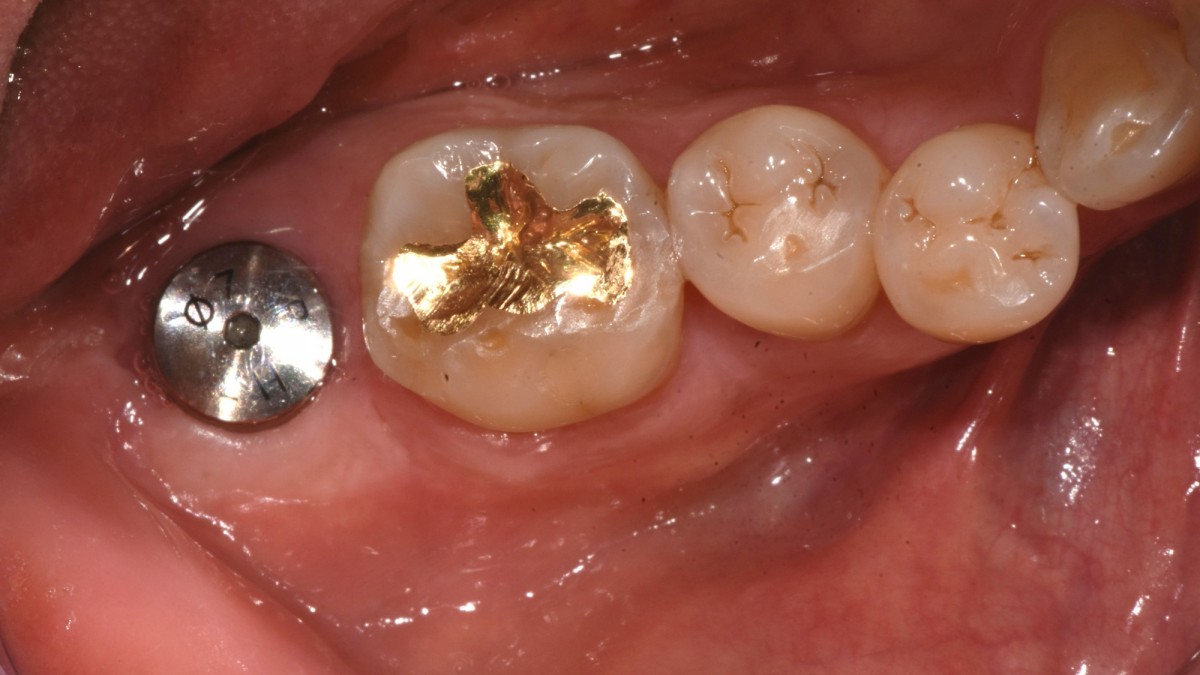

A 47-year-old male patient had a crown with an ill-fitting margin and crack-tooth syndrome in the lower 2nd molar. No systemic issue.

▲extraction

▲Arum Dentistry NB1 5*10